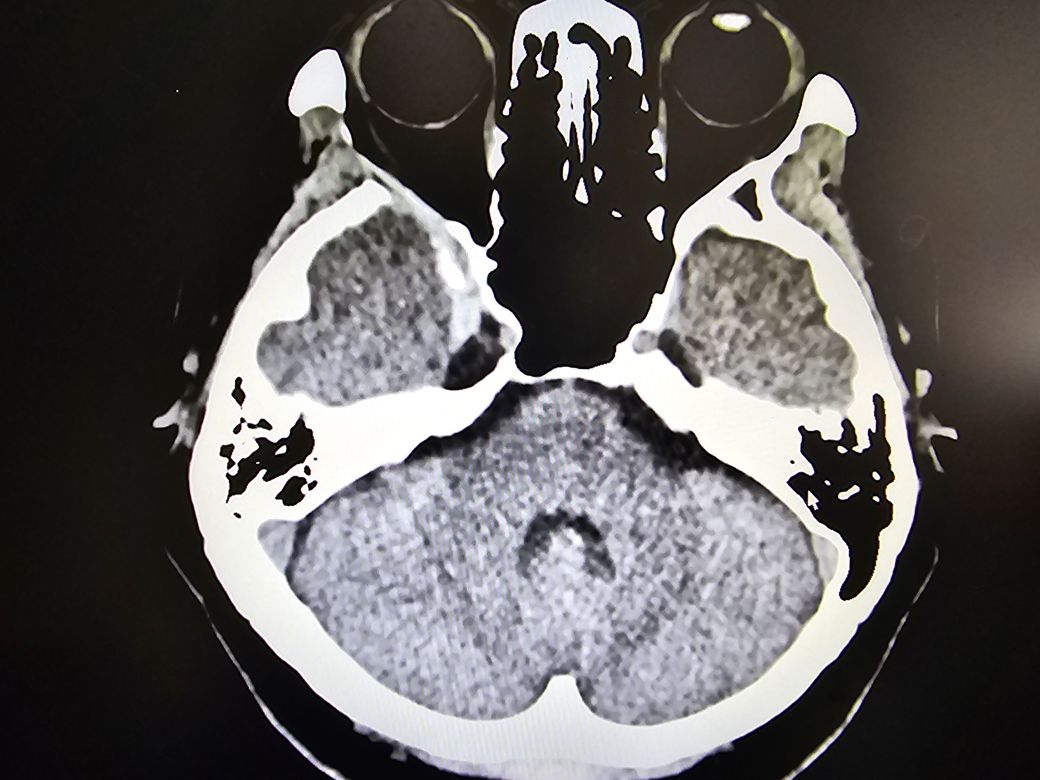

5년전에 오른쪽 뇌에 양성 뇌종양수술을 했고 얼마전 아침마다 일주일이상 같은 시간에 같은 증상의 쇠신이마두통이 심해서 준종합병원에서 ct를 찍었는데 종양이 재발됐고 8.6미리라고 하셨고 수술한 병원에서 다시 mri를 찍어보고 감마나이프 수술을 하라고 하셨는데 불안한 마음이 질문드립니다.

안녕하세요. 영상의학과 전문의 최원제 의사입니다.

올려주신 사진만으로는 뇌종양 여부를 판단하기가 어렵습니다.

CT를 찍은 준종합병원에서 판독이 나왔을 테니, 판독지를 확인해보시기 바랍니다.